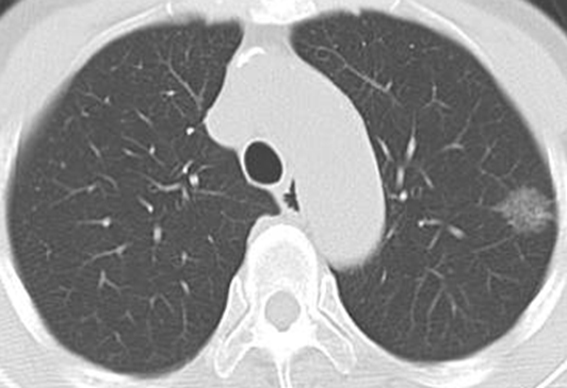

近年増加しているタバコを吸わない女性に多い「肺腺がん」とは、ごく早期のすりガラス陰影といわれるCT検査でしか見えないようながんで、周辺部の影が淡く、直径1.5cm以下であれば、日本肺癌学会のガイドラインでは経過観察でよいとされています。比較的おとなしいがんで、1cm以下のすりガラス状の肺腺がんで女性の場合は、5年後にがんが大きくなっている人は1割程度で、残りの9割の人は大きくならないで、なかには一生そのままの状態の人もいたとの報告もあります。経過観察して、たとえば5年たって大きくなったならその時に、肺を部分的に切除する手術をすればよく、術後の抗がん剤治療も必要ありません。ただ、肺の正常な部分とがん化したすりガラス状に映る影との境界線がはっきりしていたり、影の中にくっきりした部分が広がっている場合は早期ではない可能性があり、注意が必要です。さらに、多発しやすいという性質もあります。

バコを吸わない女性に多い肺がんのCT画像